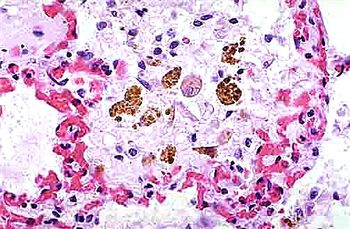

小鼠肺泡巨噬細(xì)胞的應(yīng)用

巨噬細(xì)胞,作為免疫系統(tǒng)中的重要成員,以其獨(dú)特的吞噬能力和廣泛的生物學(xué)功能,在機(jī)體的免疫防御、組織修復(fù)、炎癥反應(yīng)調(diào)控等方面發(fā)揮著至關(guān)重要的作用。